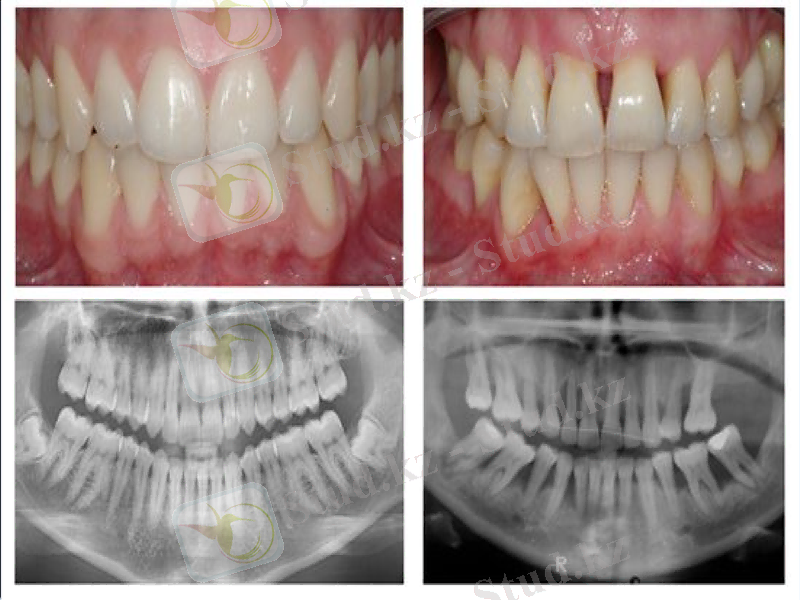

Әр дәрежедегі пародонтоз

Ремиссия сатысындағы және әс дәрежедегі пародонттың қабынуы

Пародонт тіндерінде қабыну үрдісінің клиникалық белгілердің болмауы. Қызылиек жиегі ашық-қызғылт түсті. Ауырлық дәрежесіне байланыстытіс түбірінің жалаңаштануы. Ортопантомограммада: альвеолааралық қылқындардың биіктігінің төмендеуі.

Пародонтоздың пародонтиттен ерекшелігі тіс қатарында тіс түбірі және мойнының біркелкі жалаңаштануы, тіс түбірінің айқын жалаңаштануы кезінде де тіс қозғалғыштығының болмауы. Ортопантомограммада: пародонтитте альвеолааралық қылқандар биіктігінің біркелкі емес төмендеуі, ал пародонтозда біркелкі, сүйек кемігі ұсақұяшықты құрылым тән (остеосклероз)